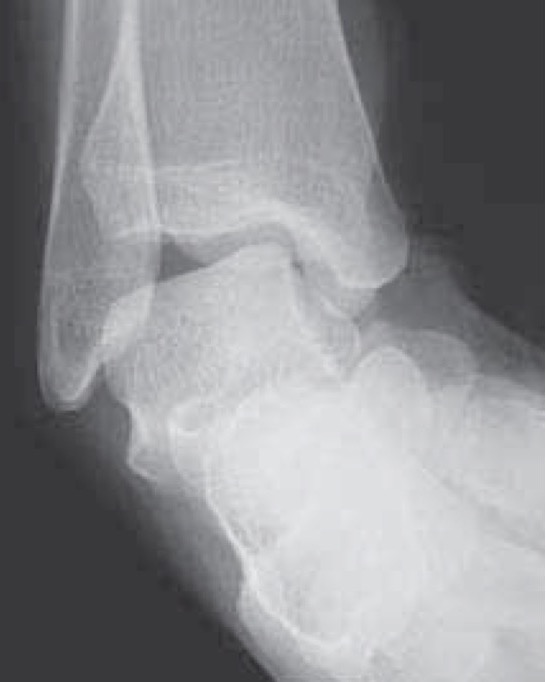

Xrays

Osteochondral lesions

Loose bodies

Stress Xrays